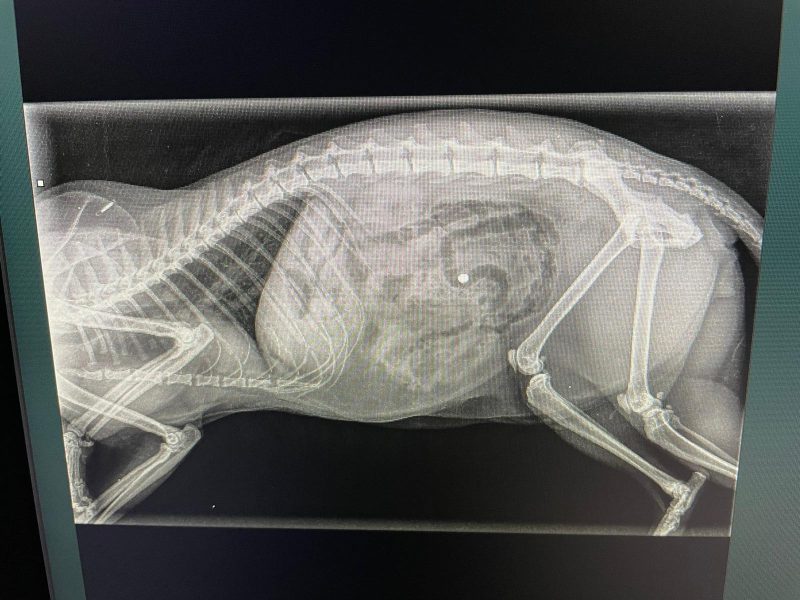

Kat Angel (12) doorboord met kogel uit luchtbuks, baasjes ontredderd

Zoals de meesten al gelezen hebben kwam Angel gistermorgen in heel kritieke toestand bij ons centrum binnen in de armen van het baasje. We wisten in eerste instantie niet wat er met haar aan de hand was. Zou ze vergiftigd zijn, aangereden of misschien beschoten. Op de foto’s was de kogel duidelijk zichtbaar. De kogel…